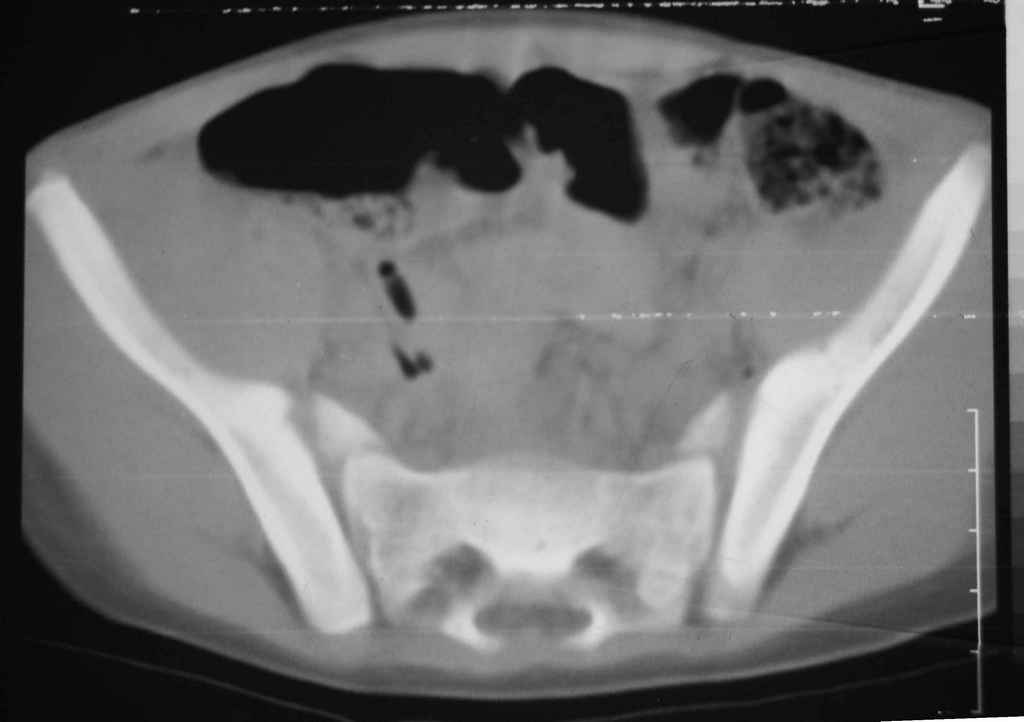

Перелом вертлужной впадины

Уважаемые коллеги, помогите определиться с тактикой лечения.Ребёнок 7 лет, травма 11.09.08, поступил с травматическим вывихом бедренной кости.

Вывих вправлен, конечность фиксирована на скелетном вытяжении. Что делать с переломом подвздошной кости? Лечить консерватино или оперировать?